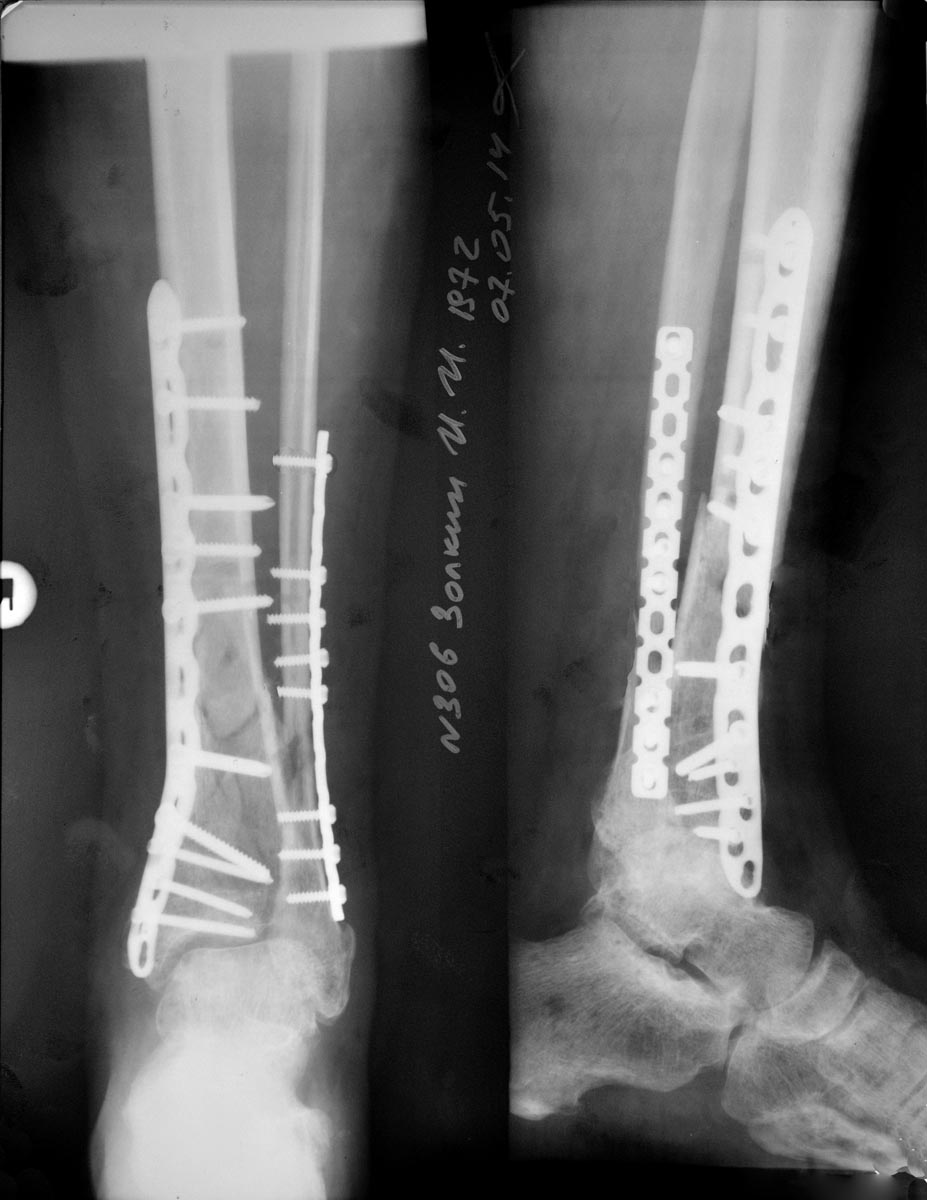

Просмотрел насчет даты операции - уже указано. На представленных апрельских снимках резорбция вокруг дистальных винтов, оперировать однозначно стоит.

1. Качество остеосинтеза. Пластина с угловой стабильностью. Нижние винты практически все монокортикально. Стабильность скорее относительная. Для оскольчатого перелома это хорошо.

Вопрос в том, насколько атравматично выполнена операция.

2. Ротационной деформации нет

3. Ось конечности. Если судить по снимкам, ( нарисовал во вложении легкий вальгус градусов в 5)

4. Однако судить про ось конечности сложно, так как на снимке лишь небольшой участок конечности.

5. А если вспомнить те времена, когда мы лечили лишь скелетным вытяжением, читая книги Ключевского, Каплана и Уотсона Джонса, и мысленно убрать имплант (другой снимок во вложении) мы бы сочли стояние отломков допустимым?

Снимки послеоперационные. Ранний послеоперационный период протекает без особенностей.

На снимках все неплохо. Самый дистальный винт в последующем возможно лучше будет убрать. Для репозиции большеберцовой хватило медиального разреза? или делали дополнительный?

Репозицию большеберцовой делал по медиальному доступу, по старому рубцу. Без проблем. Дистальный винт стоит субхондрально, но в сустав не проникает. Смотрели полипозиционно. Но с Вами согласен, перед началом нагрузки, скорее всего его уберу во избежании миграции в сустав.